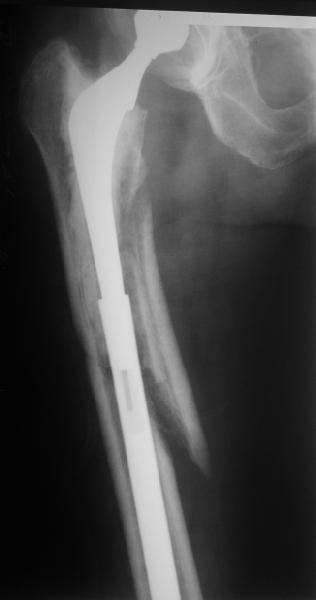

Female, rheumatoid, THA in 2003, car accident in 2006, failed plating. Nailing in Oct 2007. The nail is solid with hollow proximal part where the stem is docked. Last images are in 1 year after

nailing.

Спасибо за обсуждение. После нескольких дней тракции аппаратом сделали. Попытка закрытой репозиции не удалась из-за смещения по ширине, мешали фрагменты цемента. После их удаления репозиция получилась. Еще убрали немного цемента с ножки по латерльной стороне, чтобы обнажить 40-50 мм ее дистальной части, для плотной посадки гвоздя. Дальнейшее введение гвоздя было несложным. Протез показался нам стабильным в проксимальной части как латерально, так и медиально. Картинки в приложении.

THX for the discussion. After few days of traction by ex-fix the surgery was performed. An attempt of closed nailing was unsuccesful because of fragment translation, which was blocked by cement fragments. After removal of broken cement pieces reduction was reached "automagically". Also some cement from lateral part was removed by

chisel to expose distal 40-50 mm of the stem to allow tight fit of the nail. Further fixation by the nail was pretty easy and straightforward. Images attached. The stem looked stable in its proximal part both laterally and medially. Comments/critics are welcome.

Reminded me of a case I did a couple years ago - 30 year old woman with juvenile rheumatoid arthritis and a nonunion below her stem. Fixed with retrograde nail which docked with the stem and a lateral locking plate. Image attached. One of the companies should come up with a stem design and nail system that anticipates this need.